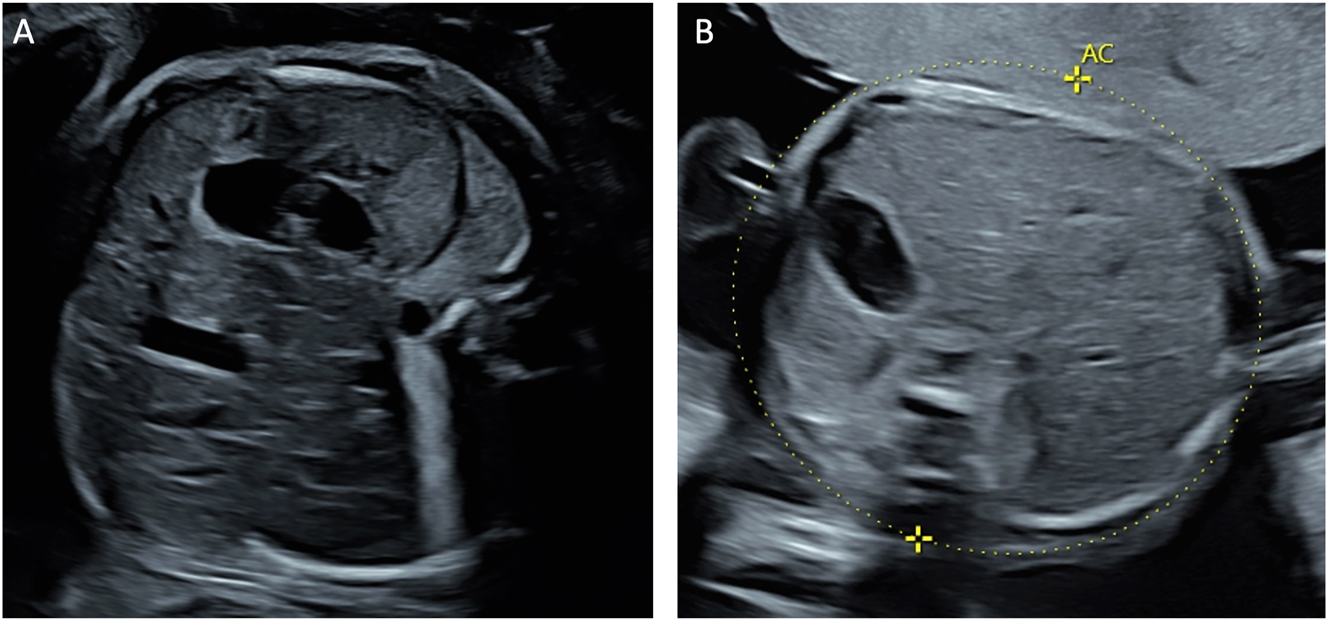

Beyond MCA-PSV measurements, several additional ultrasound findings may suggest TAPS, including differences in placental thickness and echogenicity. Typically, the donor’s placental share appears hyperechoic and thick, while the recipient’s portion presents hypoechoic and thin (Figure 5) [52]. Another characteristic finding is the ‘starry-sky liver’ appearance in the recipient twin, characterized by a hypoechoic liver parenchyma with hyperechoic portal venous walls (Figure 6) [53]. Similar to TTTS, TAPS can be classified into five stages of severity (Table 2) [50]. For early detection of TAPS, ultrasound examinations are recommended fortnightly beginning at 16 weeks’ gestation. Upon diagnosis of TAPS, weekly ultrasound monitoring is indicated [49].

Figure 6:

Ultrasound appearance of the liver in twin-to-twin transfusion syndrome. (A) Abdomen of the polycythemic recipient twin showing hypoechoic liver parenchyma with hyperechoic portal venous walls, known as the ‘starry-sky’ liver appearance, and (B) the abdomen with the normal liver of the anemic donor twin.